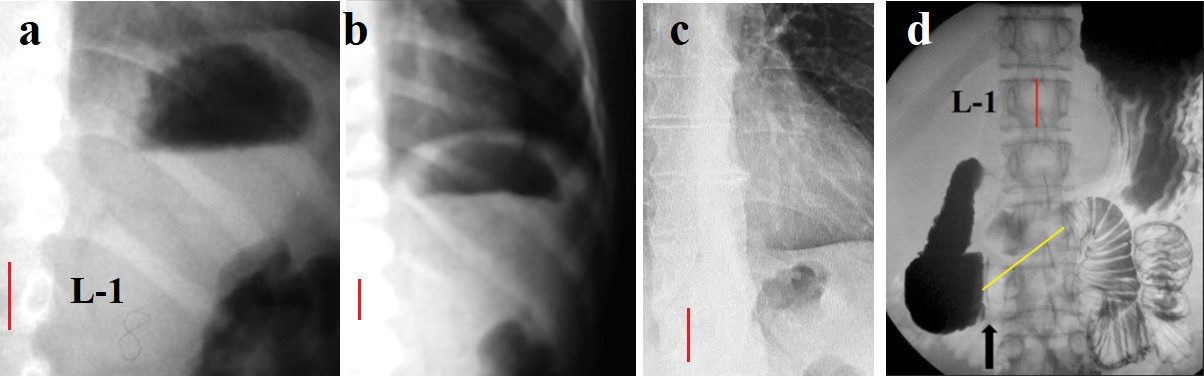

The results of each group are compared with the measurement results in group 2. The table shows that in children over 7 years of age, compared with children under 7 years of age, only the width of the GGB increases significantly, while the increase in the height of the dome was not significant. In patients of group 3, the sizes of the GGB were the same as in patients of group 2. In patients aged 16 to 64 years (group 4), both sizes of the GGB were smaller than in children, but this difference was not significant. Meanwhile, in 18% of patients in this group, the GGB was not determined at all (Figure 4). In patients aged 65 years and older (group 5), a significant decrease in both the width and height of the GGB was found. In addition, the number of patients with no GGB at all increased (25%). These data indicate that all children and adolescents have a GGB, the area of ​​which on radiographs is almost the same. With age, GGB decreases and the number of individuals without GGB gradually increases.

Figure 4. Radiographs with GGB. (a). An 8-month-old patient. (b). An 8-year-old patient. The size of the GGB in both images seems to be the same. However, the true magnitude of the GGB in figure (b) is smaller because the images were taken with different projection magnifications. (c). In the radiograph of a 56-year-old patient with GERD symptoms, the GGB is very small. (d). In the radiograph, the yellow line shows the contraction of the Ochsner sphincter. The image shows that a significant volume of gas is evacuated from the stomach into the jejunum.